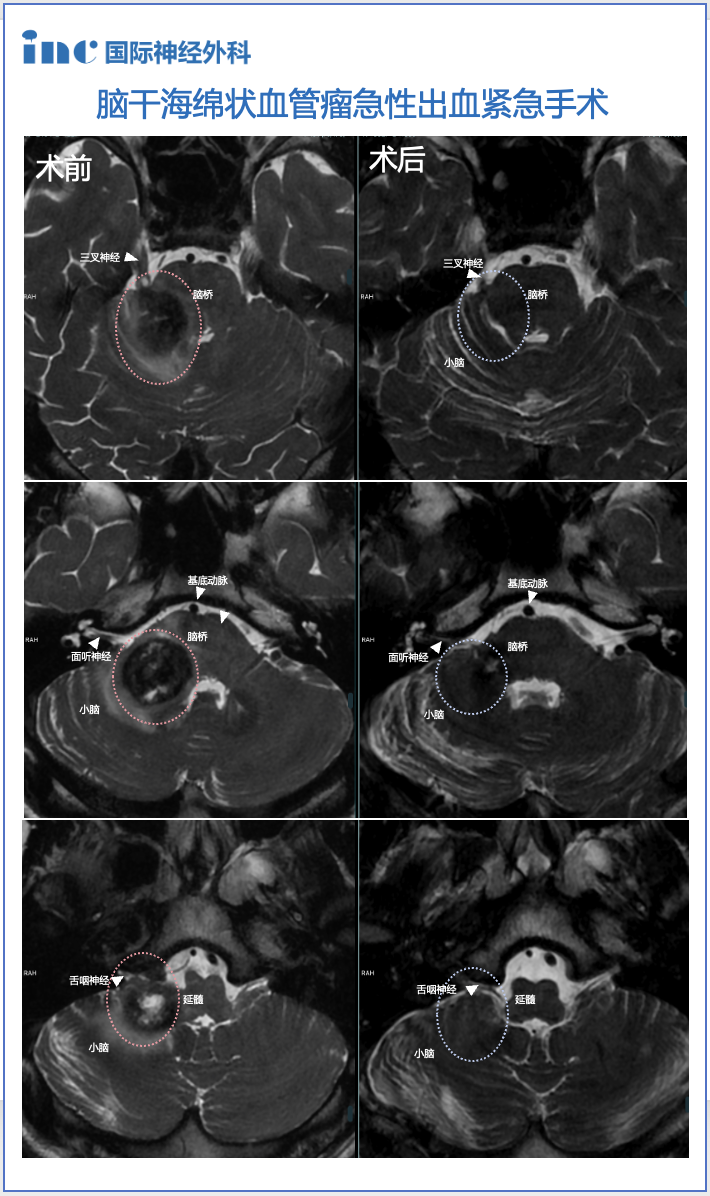

術(shù)前情況:20歲,大學(xué)生,意識(shí)紊亂并逐漸惡化,左偏癱,MRI顯示腦干中腦出血,急性梗阻性腦積水。病變位于腦干腹側(cè)中腦中線,體積為10.7立方毫米,深度為42.5mm和和11.6°的腫瘤側(cè)傾角(圖A、B)。

術(shù)后情況:術(shù)后Maritta的恢復(fù)也很順利?;颊叩囊庾R(shí)和偏癱迅速改善,腦積水消退。病人步行出院,沒有3個(gè)月后隨訪的神經(jīng)或認(rèn)知功能障礙。術(shù)后MRI顯示完全切除了軸內(nèi)血腫和血管病變(圖C、D)。

圖A和B顯示術(shù)前MRI影像

圖A和B顯示術(shù)前MRI影像,出血性中腦海綿狀血管瘤診斷明確。黃色虛線表示腫瘤深度(42.5毫米)。圖C、D顯示完全切除血管病變后的術(shù)后MRI,病變?nèi)?,壓迫占位效?yīng)解除,腦組織復(fù)位,未見手術(shù)損傷如腦出血、腦水腫等。